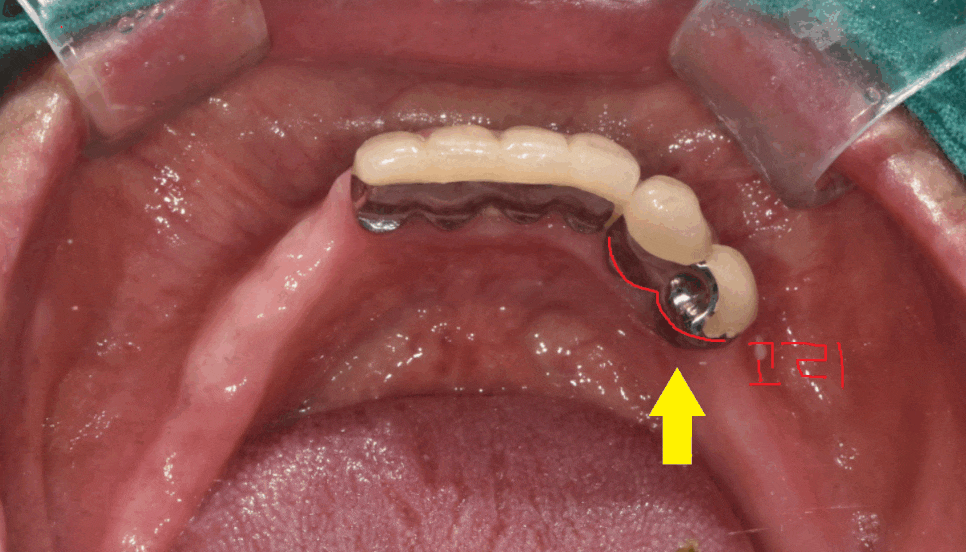

틀니 사용중 치아 부러짐으로 내원해주셨습니다.

부분 틀니를 사용할 때에

치아에 틀니를 걸어서 사용하게 되는데요

오래 사용하다보면

내 치아가 약해져 오늘 같이 부러지는 경우가 생깁니다.

아무래도 틀니를 꼈다 뺐다 하면서

걸어진 치아에 힘이 자꾸 가해져

무리를 주게 되는거죠

틀니 사용중 치아 부러짐

해결을 위해서는

부러진 정도가 중요합니다!!

환자분은 뿌리만 남았을 정도로 많이 부러져서

뽑아야했습니다.